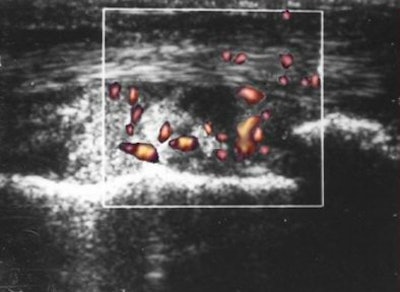

![]() |

| Baseline PDS of right knee reveals marked vascular signals. |

| Follow-up images of the same patient at the end of the second (above) and sixth (below) month after therapy demonstrate significant decrease in vascularity. |